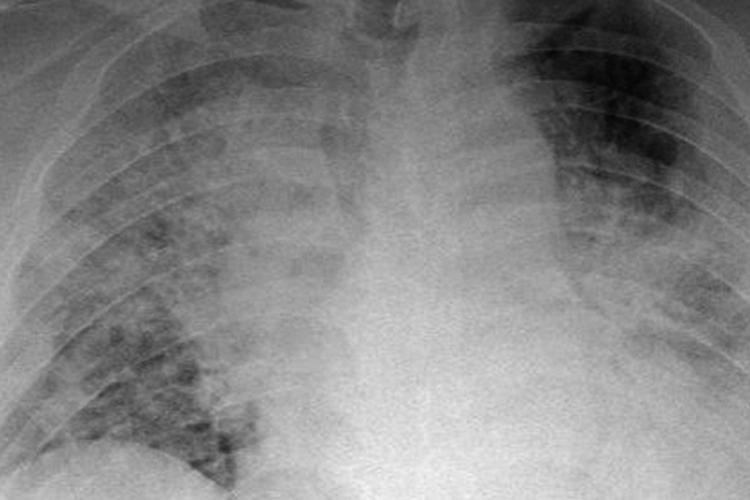

De første erfaringer med coronasyge borgere på hospitalers intensive afdelinger tegner et billede af en sygdom, som er værre for patienterne end frygtet og sværere for lægerne at tackle end ventet. De syge har brug for at være i respirator i forbavsende lang tid, ofte over to uger, i takt med at sygdommen udvikler sig uforudsigeligt med stigende risiko for, at de dør. Og det er ikke kun ældre medborgere, som bliver kritisk syge af covid-19; i enkelte tilfælde skal respiratorerne pumpe luft ned i lungerne på unge i 20’erne.

Et typisk billede er, at når patienten er kommet i respirator, går der nogle dage, hvorefter patienten får meget svært ved at få respiratorens ilt fra lungerne ud i blodet, så lægerne må skrue markant op for ilt og indblæsningskraft. Efter bedring kommer et nyt dyk, sygdommen udvikler sig cyklisk, imens patientens immunforsvar kæmper en ulige kamp mod en virus, det aldrig har mødt før.

Joachim Hoffmman-Petersen er formand for anæstesi- og intensivlægernes faglige selskab, DASAIM. På baggrund af oplysninger fra lægekolleger i Danmark og egne erfaringer som uddannelsesansvarlig overlæge på anæstesi- og intensivafdelingen på Svendborg Sygehus konstaterer han, at »covid-19 er en led sygdom, som ødelægger lungernes evne til at få ilt ud i blodbanen«, og at »patienterne er tæt på muren (80 til 100 procent ilt på respiratoren) i forbavsende lang tid«. Overlægen forventer, at nogle kommer til at ligge i respirator i både 3, 4 og 5 uger, før de enten dør eller overlever.